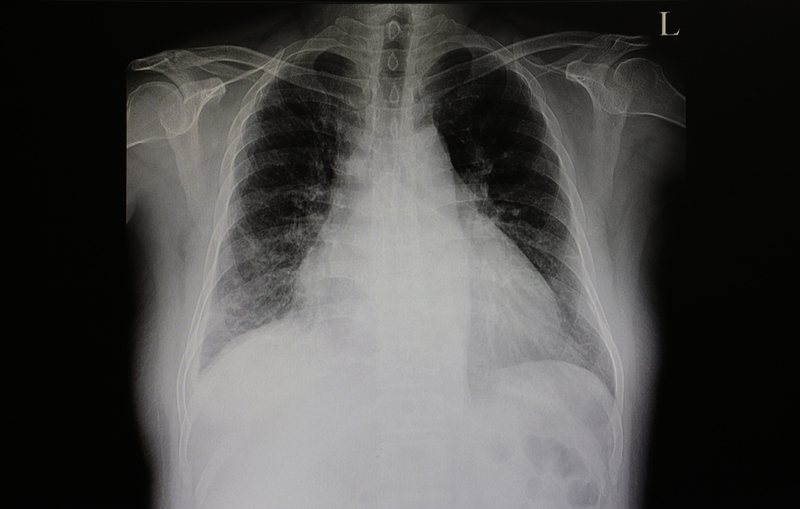

Simply put, heart failure is when the heart muscle doesn't function properly in its squeezing or relaxing functions. "To combat this disturbing trend, we need to focus on improving the control of risk factors, including blood pressure, cholesterol and diabetes," said Khan.